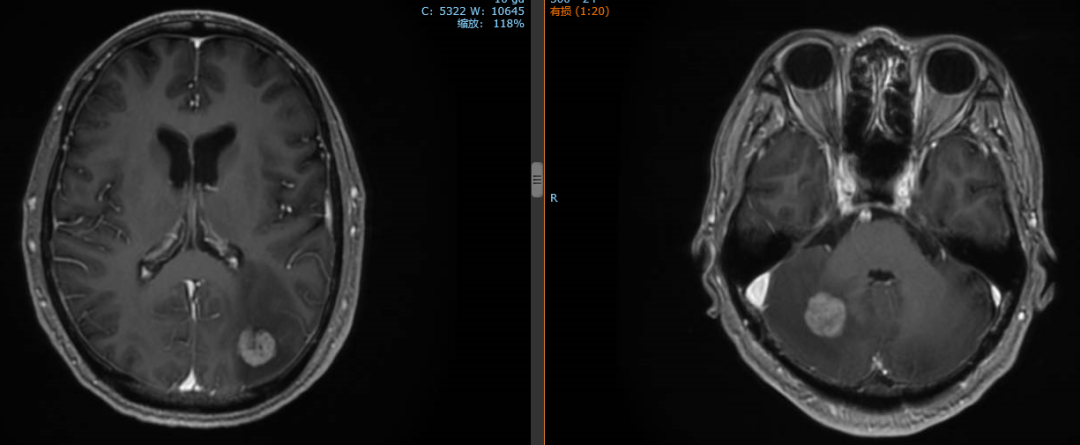

2020年1月患者出现头痛症状,复查脑MR示:枕叶及右侧小脑半球多发结节,结合病史考虑转移灶。

经影像学评估后,患者肝脏、双肺、颈部淋巴结无进展。

2020年1月13日开始对左侧枕叶及右侧小脑转移灶进行放疗,PTV-GTV=44.5Gy/9F

患者继续行赫赛汀+希罗达维持治疗方案。但因新冠肺炎疫情,2020.1~2020.4赫赛汀治疗中断。